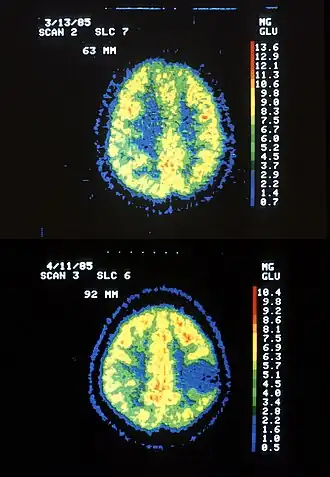

boven gezonde hersenen, onder met astrocytomen | ||||